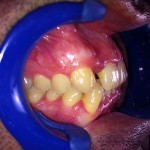

Este é um caso mais simples de se fazer e com um valor (custo-benefício) bastante cómodo.São somente 4 implantes na arcada inferior suportando uma barra sobre a qual será transferido em parte o esforço mastigatório. É confeccionada em RESINA como uma prótese total convencional.